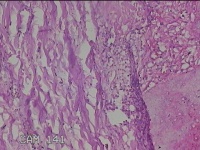

右侧腰臀部包块

性别

女

年龄

44岁

临床诊断

臀部良性肿瘤

一般病史

发现右侧腰臀部包块1个月余。

标本名称

大体所见

灰白粉红色包块0.8x0.3x0.2cm一个,表面光滑。

良性病变。